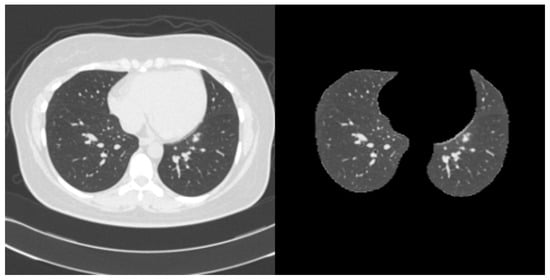

Lung Opacity Segmentation in Chest CT Images Using Multi-Head and Multi-Channel U-Nets with Partially Supervised Learning

by Shingo Mabu, Takuya Hamada, Satoru Ikebe and Shoji Kido

Appl. Sci. 2025, 15(19), 10373; https://doi.org/10.3390/app151910373 - 24 Sep 2025

There has been a large amount of research applying deep learning to the medical field. However, obtaining sufficient training data is challenging in the medical domain because annotation requires specialized knowledge and significant effort. This is especially true for segmentation tasks, where preparing [...] Read more.

There has been a large amount of research applying deep learning to the medical field. However, obtaining sufficient training data is challenging in the medical domain because annotation requires specialized knowledge and significant effort. This is especially true for segmentation tasks, where preparing fully annotated data for every pixel within an image is difficult. To address this, we propose methods to extract useful features for segmentation using two types of U-net-based networks and partially supervised learning with incomplete annotated data. This research specifically focuses on the segmentation of diffuse lung disease opacities in chest CT images. In our dataset, each image is partially annotated with a single type of lung opacity. To tackle this, we designed two distinct U-net architectures: a multi-head U-net, which utilizes a shared encoder and separated decoders for each opacity type, and a multi-channel U-net, which shares the encoder and decoder layers for more efficient feature learning. Furthermore, we integrated partially supervised learning with these networks. This involves employing distinct loss functions to both bring annotated regions (ground truth) and segmented regions (predictions) closer, and to push them apart, thereby suppressing erroneous predictions. In our experiments, we trained the models on partially annotated data and subsequently tested them on fully annotated data to compare the segmentation performance of each method. The results show that the multi-channel model applying partially supervised learning achieved the best performance while also reducing the number of weight parameters. Full article